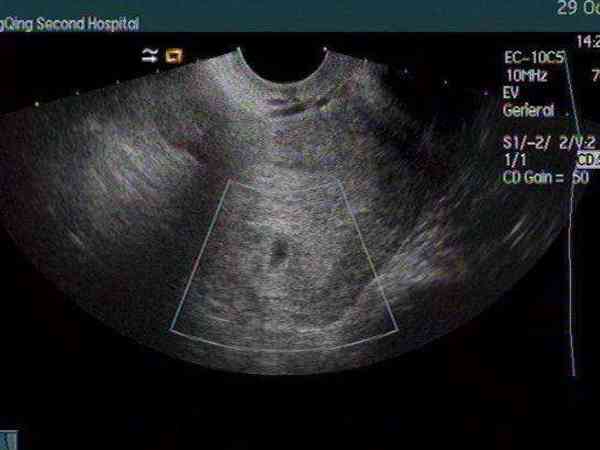

目前国家政策不允许医生将胎儿性别告知给家长,那么一些好奇的孕妈相知道胎儿的性别该怎么办呢。孕检时,怀孕40天左右通过B超就可以看到胎囊了,传言通过检查报告单上孕囊的大小形状,就可以判断宝宝是男孩还是女孩。胎囊形状怎么准确看男女从医学的角度来看,胎囊的形状判断不了男孩还是女孩,因为胎囊的选择受到怀孕时间、发育情况以及子宫的形状等因素影响,大多数孕囊都是椭圆形或月亮形,但是,随着怀孕时间的增加孕囊发育...